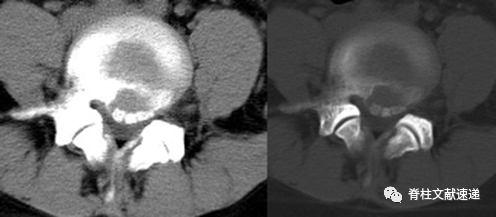

上图为笔者临床所见病例资料,与B型相近。